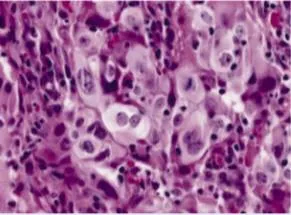

Anaplasia: The Hallmarks of High-Grade Malignancy

Anaplasia (Greek: "to form backward") represents loss of structural and functional differentiation:

- Nuclear abnormalities - most reliable indicators

- Nuclear pleomorphism: variation in nuclear size and shape

- Hyperchromasia: dark-staining nuclei (increased DNA content)

- Increased nuclear-to-cytoplasmic (N:C) ratio: >1:4 (normal 1:6-1:8)

- Coarse chromatin clumping: irregular DNA distribution

- Prominent nucleoli: often multiple, >3 μm diameter

- Cellular abnormalities

- Cellular pleomorphism: marked variation in cell size and shape

- Loss of polarity: disorganized cellular arrangement

- Tumor giant cells: cells with >20 times normal diameter

- Multinucleation: cells with 2-50+ nuclei

💡 Master This: The N:C ratio provides the single most reliable microscopic criterion for malignancy. Normal cells maintain N:C ratios of 1:6 to 1:8, while malignant cells show ratios approaching 1:1 in high-grade tumors. This reflects the nuclear enlargement from DNA content abnormalities and the cytoplasmic reduction from impaired differentiation.